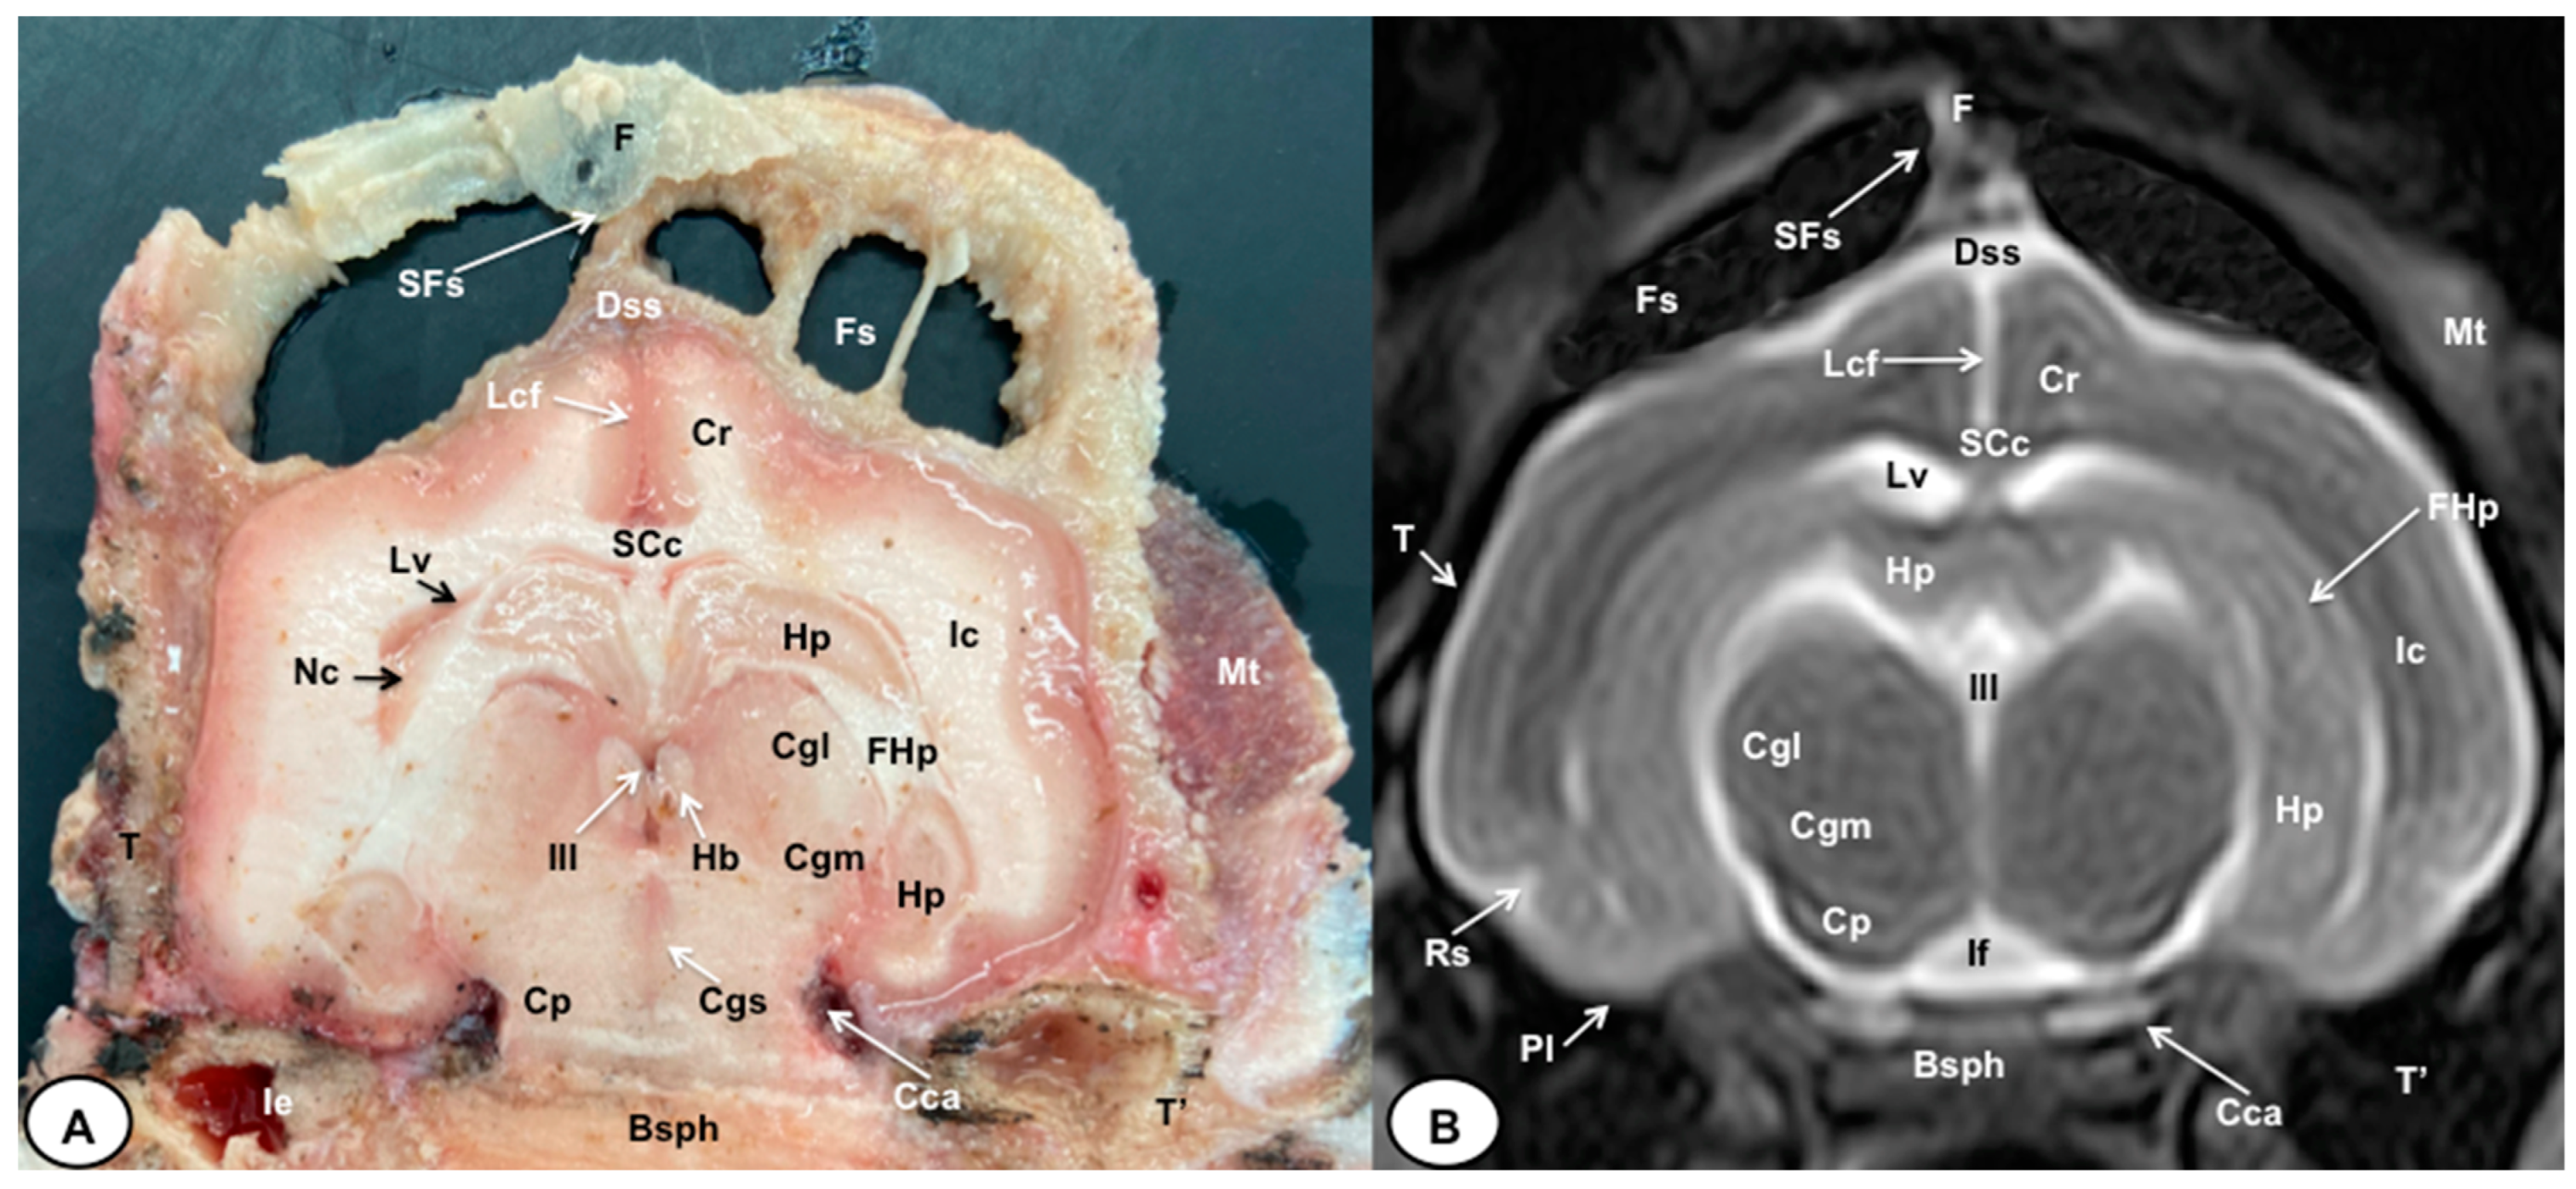

Figure 5.

Transverse cross-section (A) and T2W MR (B) images of the crested porcupine head at the level of the caudal part of the diencephalon, corresponding to line IV in Figure 1. F: frontal bone; Fs: frontal sinuses; SFs: septum of frontal sinuses; Dss: dorsal sagittal sinus; Lcf: longitudinal cerebral fissure; SCc: splenium of corpus callosum; Cr: Corona radiata; Lv: lateral ventricle; Hp: Hippocampus; FHp. fimbria of hippocampus; Nc: Nucleus caudatus (tail); Ic: internal capsule; III: third ventricle; Hb: habenula; Cgl: Corpus geniculatum laterale (lateral geniculate body); Cgm: Corpus geniculatum mediale (medial geniculate body); Cgs: central grey substance; Cp: cerebral peduncle; If: interpeduncular fossa; Rs: rhinal sulcus; Pl: piriform lobe; T: temporal bone squama; T′: tympanic and petrous parts of temporal bone; Ie: inner ear. Cca: caudal communicating artery; Bsph: basisphenoid bone; Mt: Musculus temporalis.

The anatomical sections obtained in this study allowed us to visualize the different structures belonging to the central nervous system and its associated structures, which were labeled according to the International Committee on Veterinary Gross Anatomical Nomenclature. Therefore, we identified the main components of the brain (the prosencephalon, mesencephalon, and rhombencephalon). Thus, the two telencephalic hemispheres surrounded by the cerebral cortex and separated by the longitudinal cerebral fissure were identified (Figure 5A, Figure 6A and Figure 7A). Both hemispheres were connected by fibers of white matter known as the corpus callosum (Figure 4A, Figure 5A, Figure 6A and Figure 7A). Each cerebral hemisphere contained a lateral ventricle (Figure 4A, Figure 5A, Figure 6A and Figure 7A). Ventrally, we distinguished a component of the basal ganglia, the nucleus caudatus (Figure 4A and Figure 5A). Thus, we identified different parts of it, such as the head and the tail. Other structures which we observed were the septal nuclei, which were circumscribed by two parallel vertical lines through the most inferior and medial aspect of each lateral ventricle (Figure 4A). More caudally, the diencephalon enclosing the third ventricle was identified, as well as more ventrally specific components of the hypothalamus, such as the optic chiasm (Figure 4A and Figure 5A). Additionally, these sections were quite helpful in showing the caudal parts of the thalamus. Hence, the lateral eminence on the caudodorsal surface of the thalamus, known as the lateral geniculate body, was distinguished, whereas caudoventrally, we identified the medial geniculate body of the thalamus (Figure 5A). Moreover, the dorsal part of the mesencephalon with the caudal and rostral colliculus and its ventral part with the cerebral peduncles were also shown (Figure 6A and Figure 7A). These anatomical sections were helpful in identifying the vermis and the cerebellar peduncles, which connected the cerebellum to the adjacent brain stem and the cerebrum (Figure 7A). The ventral part of the cerebellum with the lingula, covering part of the fourth ventricle, could also be identified (Figure 7A). These sections were also helpful in distinguishing the medulla oblongata and the decussation of the pyramids. In addition, different bony structures comprising the neurocranium were observed, such as the frontal, the temporal (with its scamous, petrous, and tympanic parts), the sphenoid, and the occipital bones (Figure 2A, Figure 3A, Figure 4A, Figure 5A, Figure 6A and Figure 7A). Furthermore, these sections showed different air-filled spaces, such as the frontal and the sphenoidal sinuses (Figure 2A, Figure 3A, Figure 4A, Figure 5A, Figure 6A and Figure 7A), and structures associated with the nasal cavity, including the ethmoturbinates and the vomer, could be distinguished (Figure 2A and Figure 3A). Main sensory organs such as the eyeball and its associated structures were also depicted. Consequently, we identified the retina, the vitreous chamber, and the optic nerve, which were surrounded by extraocular muscles. Among these, we distinguished the dorsal and ventral rectus muscles (Figure 2A). Moreover, the main components of the auditory system, such as the external auditory canal, the tympanic cavity, and the inner ear, were visualized (Figure 5A and Figure 6A). Also, we identified the relevant muscles related to masticatory function, such as the temporalis, the medial and lateral pterygoid muscles, the masseter, the digastric muscle, and other important muscles, including the buccinator muscle and the longissimus capitis of the head (Figure 2A, Figure 3A, Figure 4A, Figure 5A, Figure 6A and Figure 7A).

No significant anatomic differences were identified subjectively in the three porcupines which were imaged. Most anatomic structures distinguished on T2-weighted images of the cadaver specimens matched adequately with structures identified in the corresponding anatomical cross-sections. Hence, the central nervous system structures of the porcupine head, the eyeball’s structures (vitreous humour and lens), and the masticatory muscles showed an accurate visualization using T2W MR images. Nonetheless, the bones that comprised the neurocranium, such as the frontal, the parietal, the temporal, the occipital, and the sphenoid bones, were identified with a hypointense signal (Figure 2B, Figure 3B, Figure 4B, Figure 5B, Figure 6B, Figure 7B, Figure 8 and Figure 9).

In the transverse planes of the encephalon, identifiable structures of the brain were more hyperintense than the white matter, which was more hypointense in T2W sequences (Figure 3B, Figure 4B, Figure 5B, Figure 6B and Figure 7B). Moreover, the two sagittal and dorsal (Figure 8 and Figure 9) images and the different transverse T2W images were essential to depicting the components that comprise the ventricular system, which displayed a hyperintense signal. Hence, the lateral ventricles and the dorsal and ventral parts of the third ventricle were displayed (Figure 4B, Figure 5B, Figure 6B, Figure 7B, Figure 8 and Figure 9), and among these, we observed interthalamic adhesion, limited laterally by the right and left sides of the thalamus (Figure 8A). In addition, transverse, sagittal, and parasagittal T2W images displayed with adequate detail the dorsal and ventral parts of the hippocampus (Figure 5B, Figure 6B, Figure 7B, Figure 8B and Figure 9). In addition, the tectum of mesencephalon (tectum mesencephali) with the caudal colliculus and the fourth ventricle was visualized in excellent detail (Figure 8A,B and Figure 9B). Other essential components of the CNS, such as the vermis of the cerebellum with its dorsal and ventral lobes, were distinguished in the sagittal T2W images (Figure 8A). Hence, the moderate contrast between grey and white matter was helpful in distinguishing the different lobes. Thus, the dorsal lobes of the cerebellum (the rostral and ventral culmen, the declive, the folium, the tuber, and the pyramid), as well as its ventral lobes (the lingula, the nodulus, and the uvula), were identified. In addition to these findings, we also observed the rostral and caudal cerebellar peduncles (Figure 7B and Figure 9A). This technique also facilitated an adequate resolution to be achieved with which to identify the muscles involved in the masticatory function, which have already been mentioned in the anatomical sections.